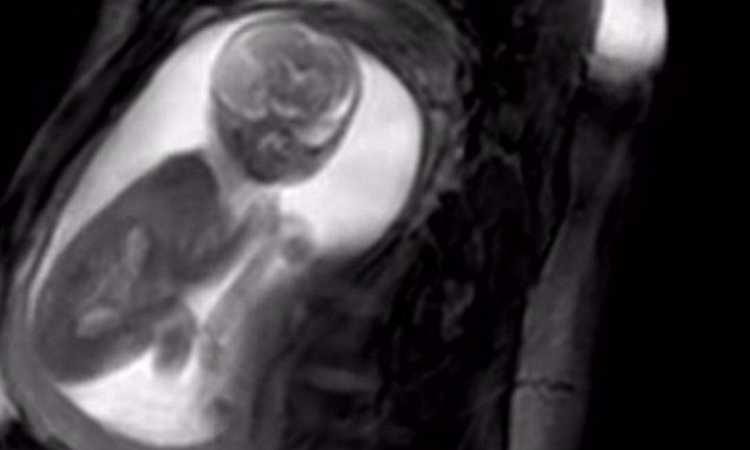

Radiation exposure to a fetus

Most of the ways a pregnant woman may be exposed to radiation, such as from a diagnostic medical exam or an occupational exposure within regulatory limits, are not likely to cause health effects for a fetus. However, accidental or intentional exposure above regulatory limits may be cause for concern.

Although radiation doses to a fetus tend to be lower than the dose to the mother, due to protection from the uterus and surrounding tissues, the human embryo and fetus are sensitive to ionizing radiation at doses greater than 0.1 gray (Gy). Depending on the stage of fetal development, the health consequences of exposure at doses greater than 0.5 Gy can be severe, even if such a dose is too low to cause an immediate effect for the mother. The health consequences can include growth restriction, malformations, impaired brain function, and cancer.